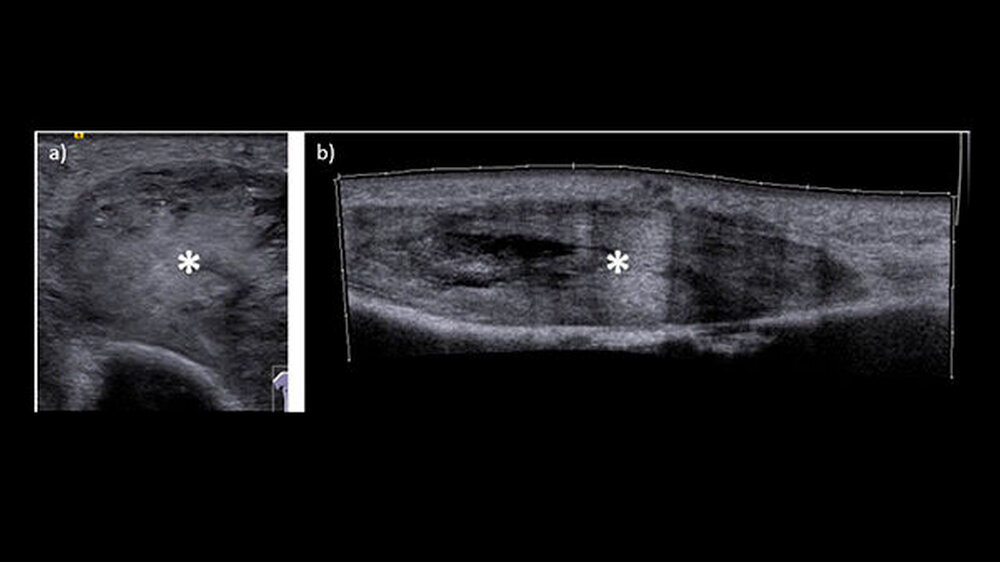

Ein Jahr nach der Exzision des Primärtumors, der begleitenden Radiatio sowie dem mikrochirurgischenAufbau des Unterkieferdefekts stellte sich der Patient erneut vor, um einen Termin zur Entfernung des Osteosynthesematerials zu vereinbaren. Bei dieser Untersuchung bemerkten die Chirurgen eine erhebliche Raumforderung am linken Oberarm, die nach Angaben des Patienten sehr schnellem Wachstum.

Weder das Röntgenbild noch die weitere Untersuchung mit magnetresonanztomografischer Bildgebung gaben eindeutigen Aufschluss. Daraufhin wurde eine Biopsie veranlasst, die die Verdachtsdiagnose einer Metastase des oralen Plattenepithelkarzinoms histologisch bestätigte.

Die Metastase wurde mittels Radiatio behandelt. Da Patienten mit Plattenepithelkarzinom und regionalen Lymphknotenmetastasen eine höhere Wahrscheinlichkeit haben, Fernmetastasen zu entwickeln und sich – nicht zuletzt wie dieser Patientenfall zeigt – auch entfernte Metastasen über die Blutwege bilden können, empfiehlt die DGMKG eine systematische Tumornachsorge mittels bildgebender Verfahren durchzuführen.